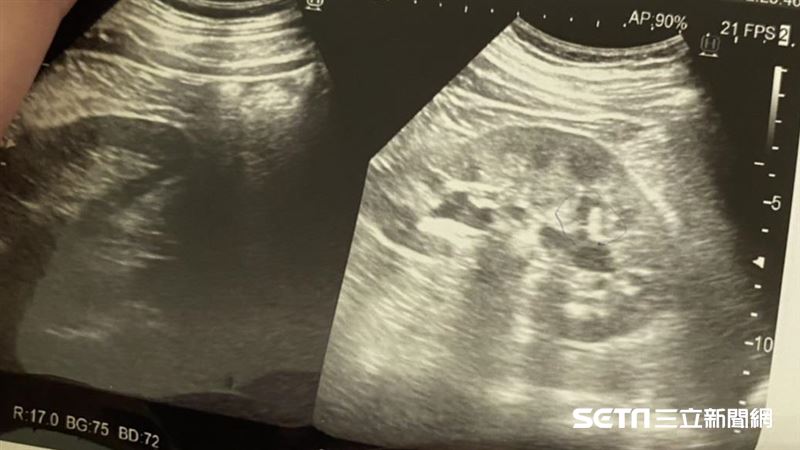

腎結石的症狀會依結石大小、位置不同而有所差異,小顆結石在初期可能幾乎沒有明顯不適,容易被忽略;但一旦結石移動或卡住尿路,症狀往往來得又急又痛。常見腎結石症狀包括:

若出現劇烈疼痛合併血尿、發燒或排尿困難,切勿自行忍耐,應盡快就醫檢查,以免延誤治療、引發感染或腎臟損傷。